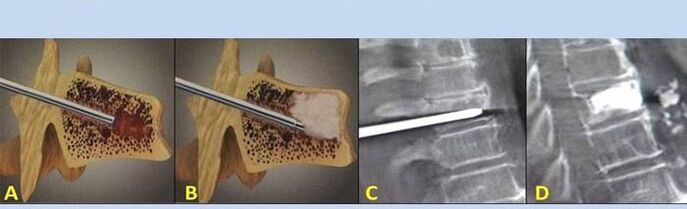

- Nucleoplasty- Removal of the intervertebral disc core.The operation relieves pressure on the nerve endings.

- Vertebroplasty puncture- Method of stabilizing the vertebrae.During the procedure, the doctor fills the spinal cavity with bone cement.